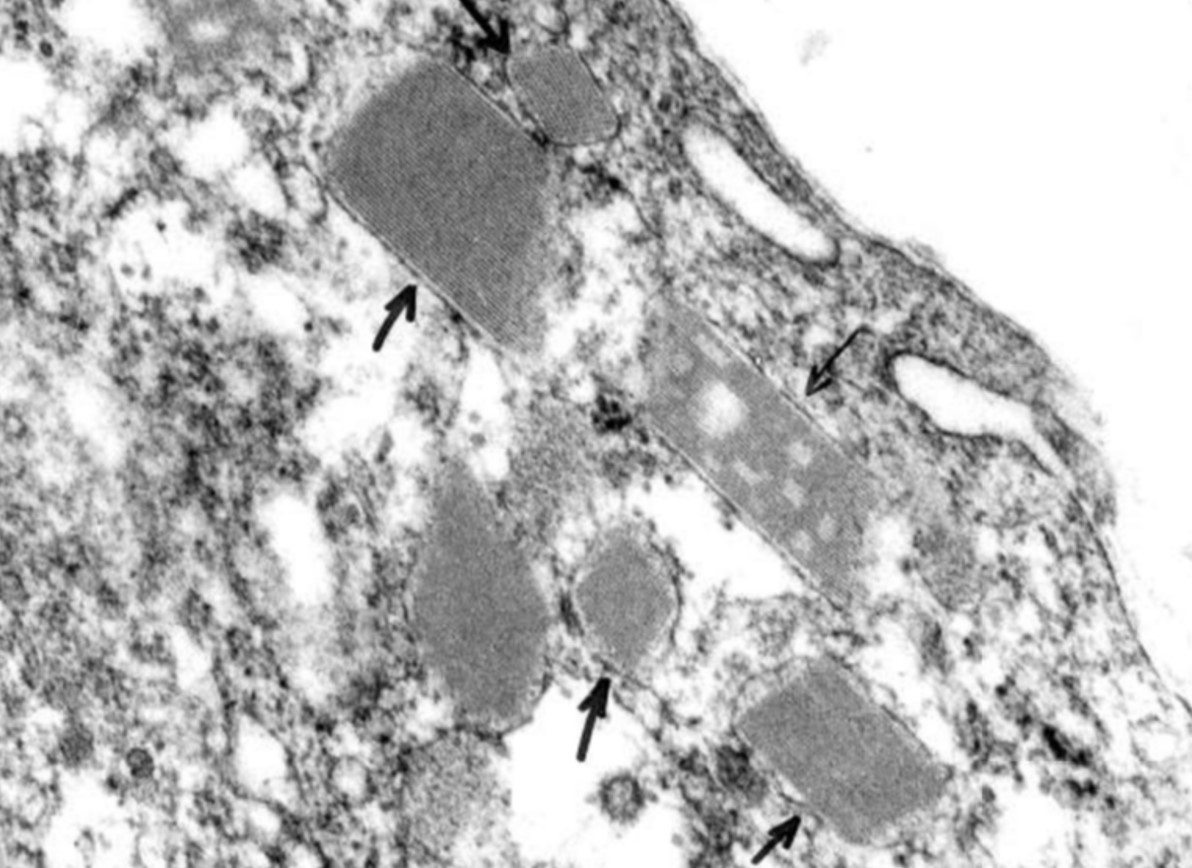

ALVEOLAR SOFT PART SARCOMA

• DISTINCTIVE LARGE POLYGONAL/RHOMBOID CRYSTALS